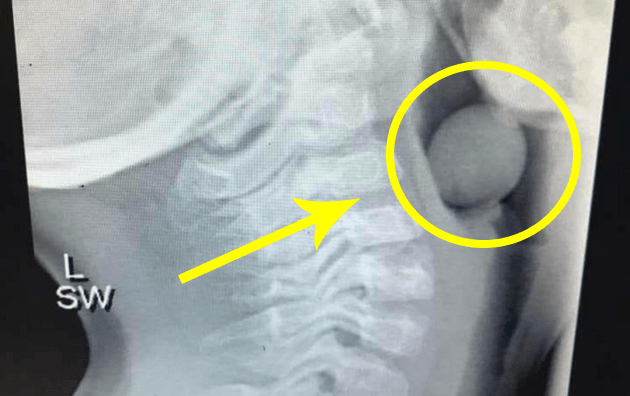

La mamma del piccolo ha accettato che il suo pediatra condividesse su Facebook la radiografia di un acino d’uva che si è incastrato nella gola di sua figlio. Per fortuna il piccolo – operato – ora sta bene, ma ha corso un grave pericolo.

Sapete cosa mostra questa radiografia? Un chicco d’uva!

Un chicco d’uva che si è posizionato all’inizio delle vie aeree di un bambino di 5 anni oggi.

Questa piccola anima è stata operata, sotto anestesia generale, per rimuovere il chicco.E’ stato molto fortunato che parte delle sue vie aeree fosse aperta altrimenti sarebbe potuta finire male.